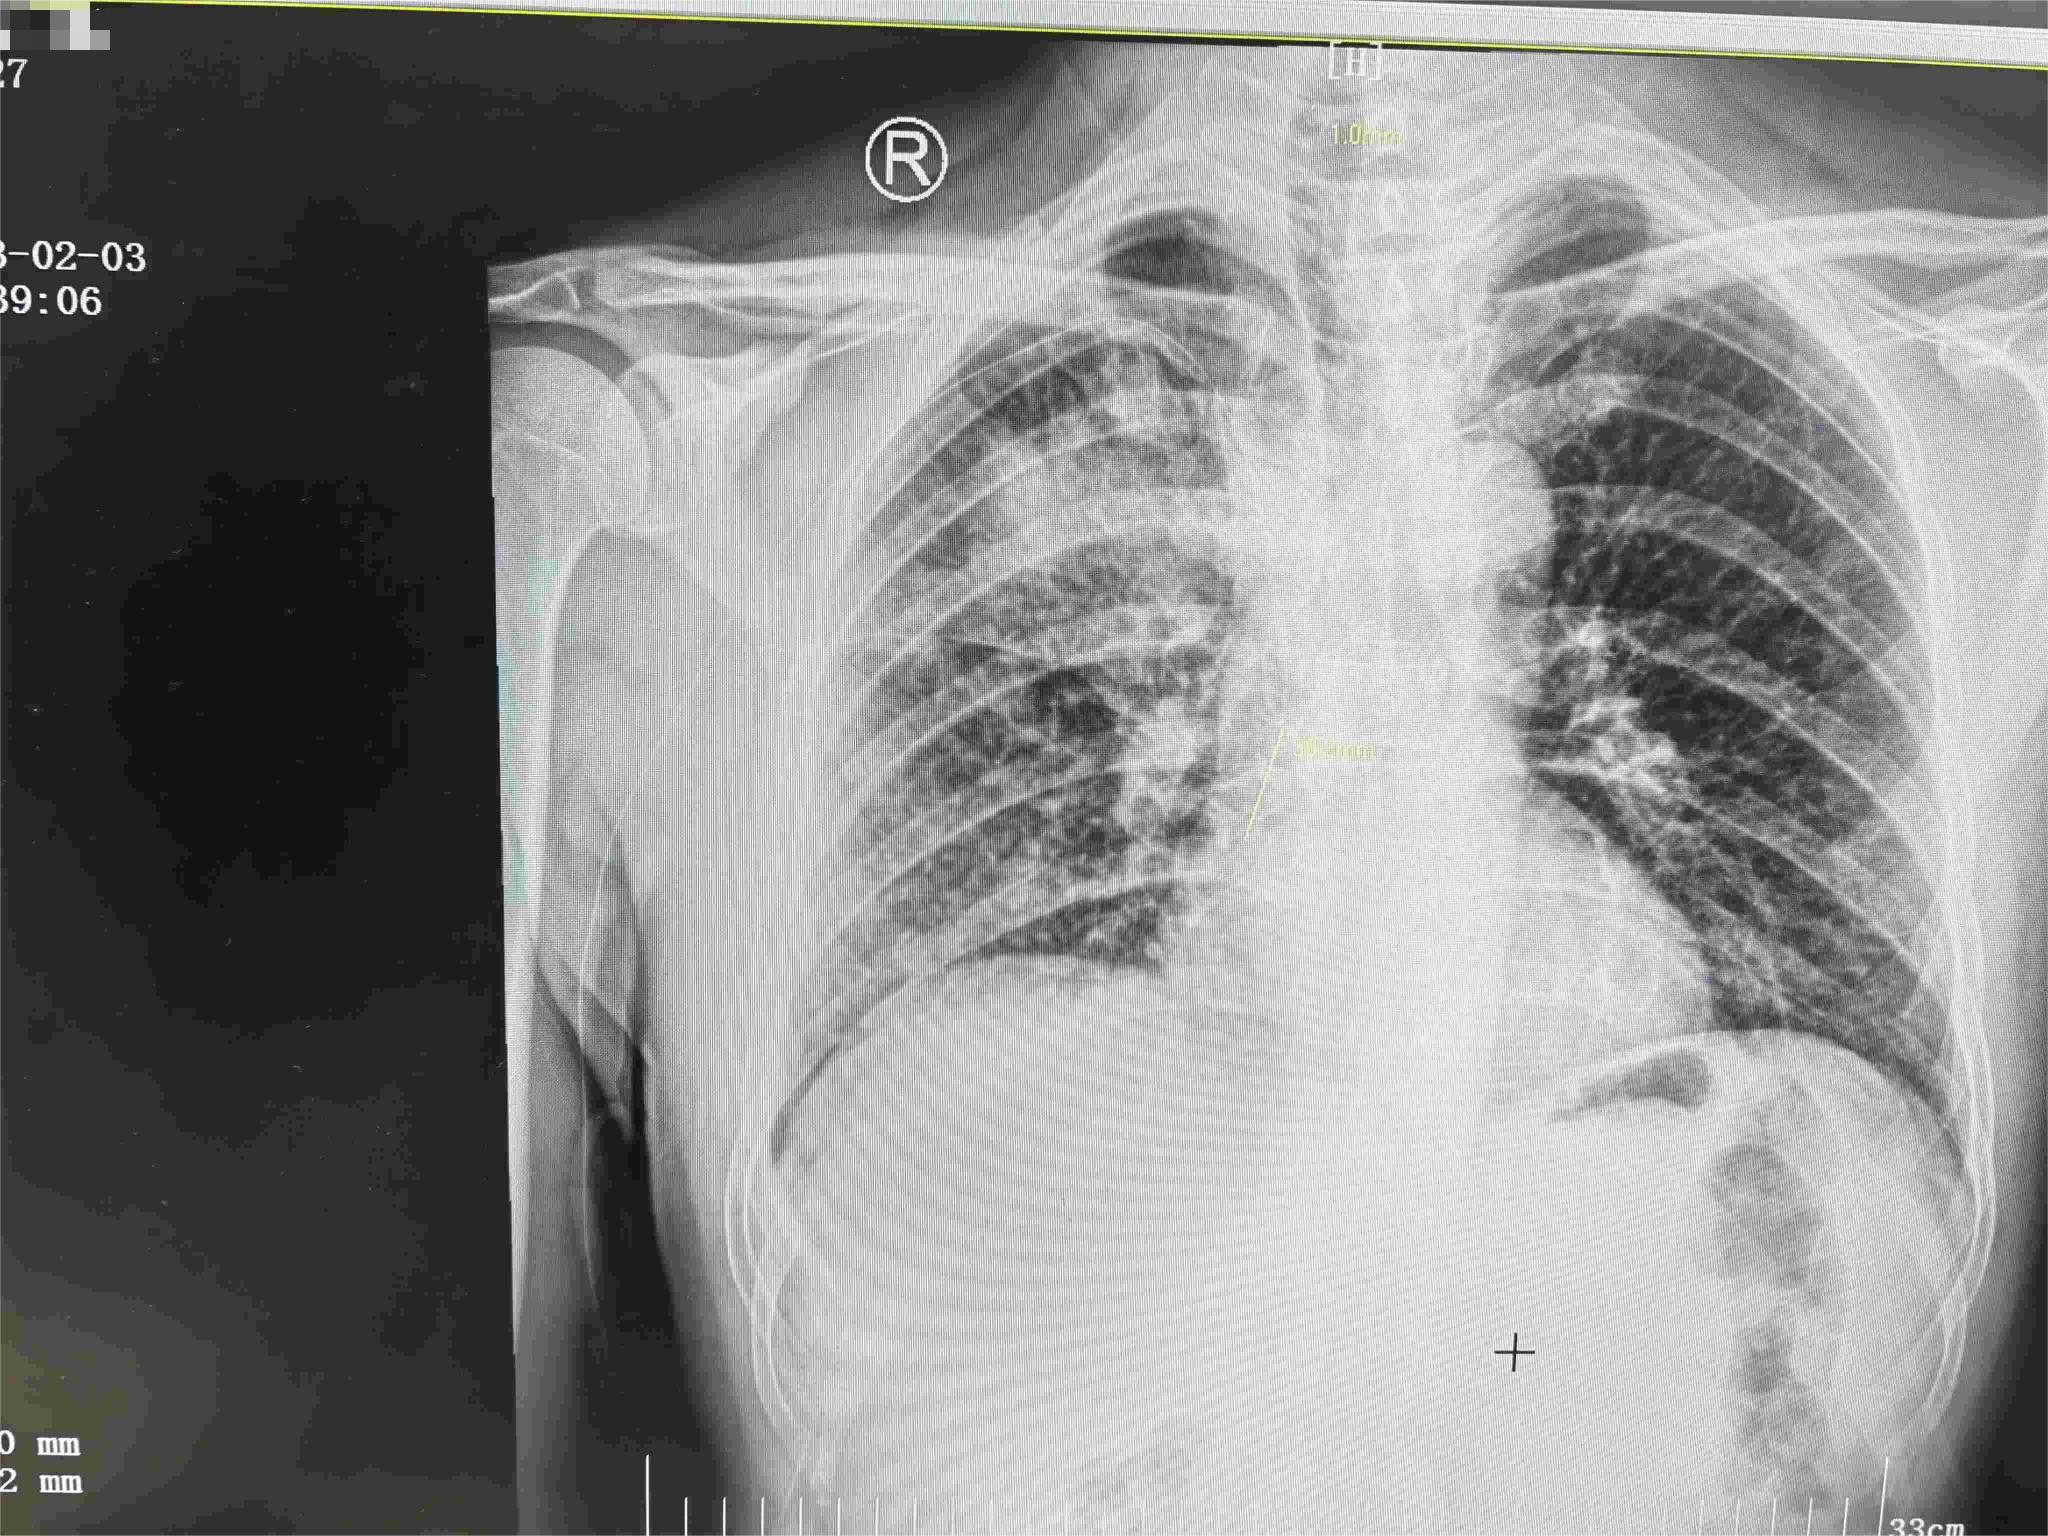

置管后通過X線平片查看PICC剪斷位置,確保尖端位于上腔靜脈